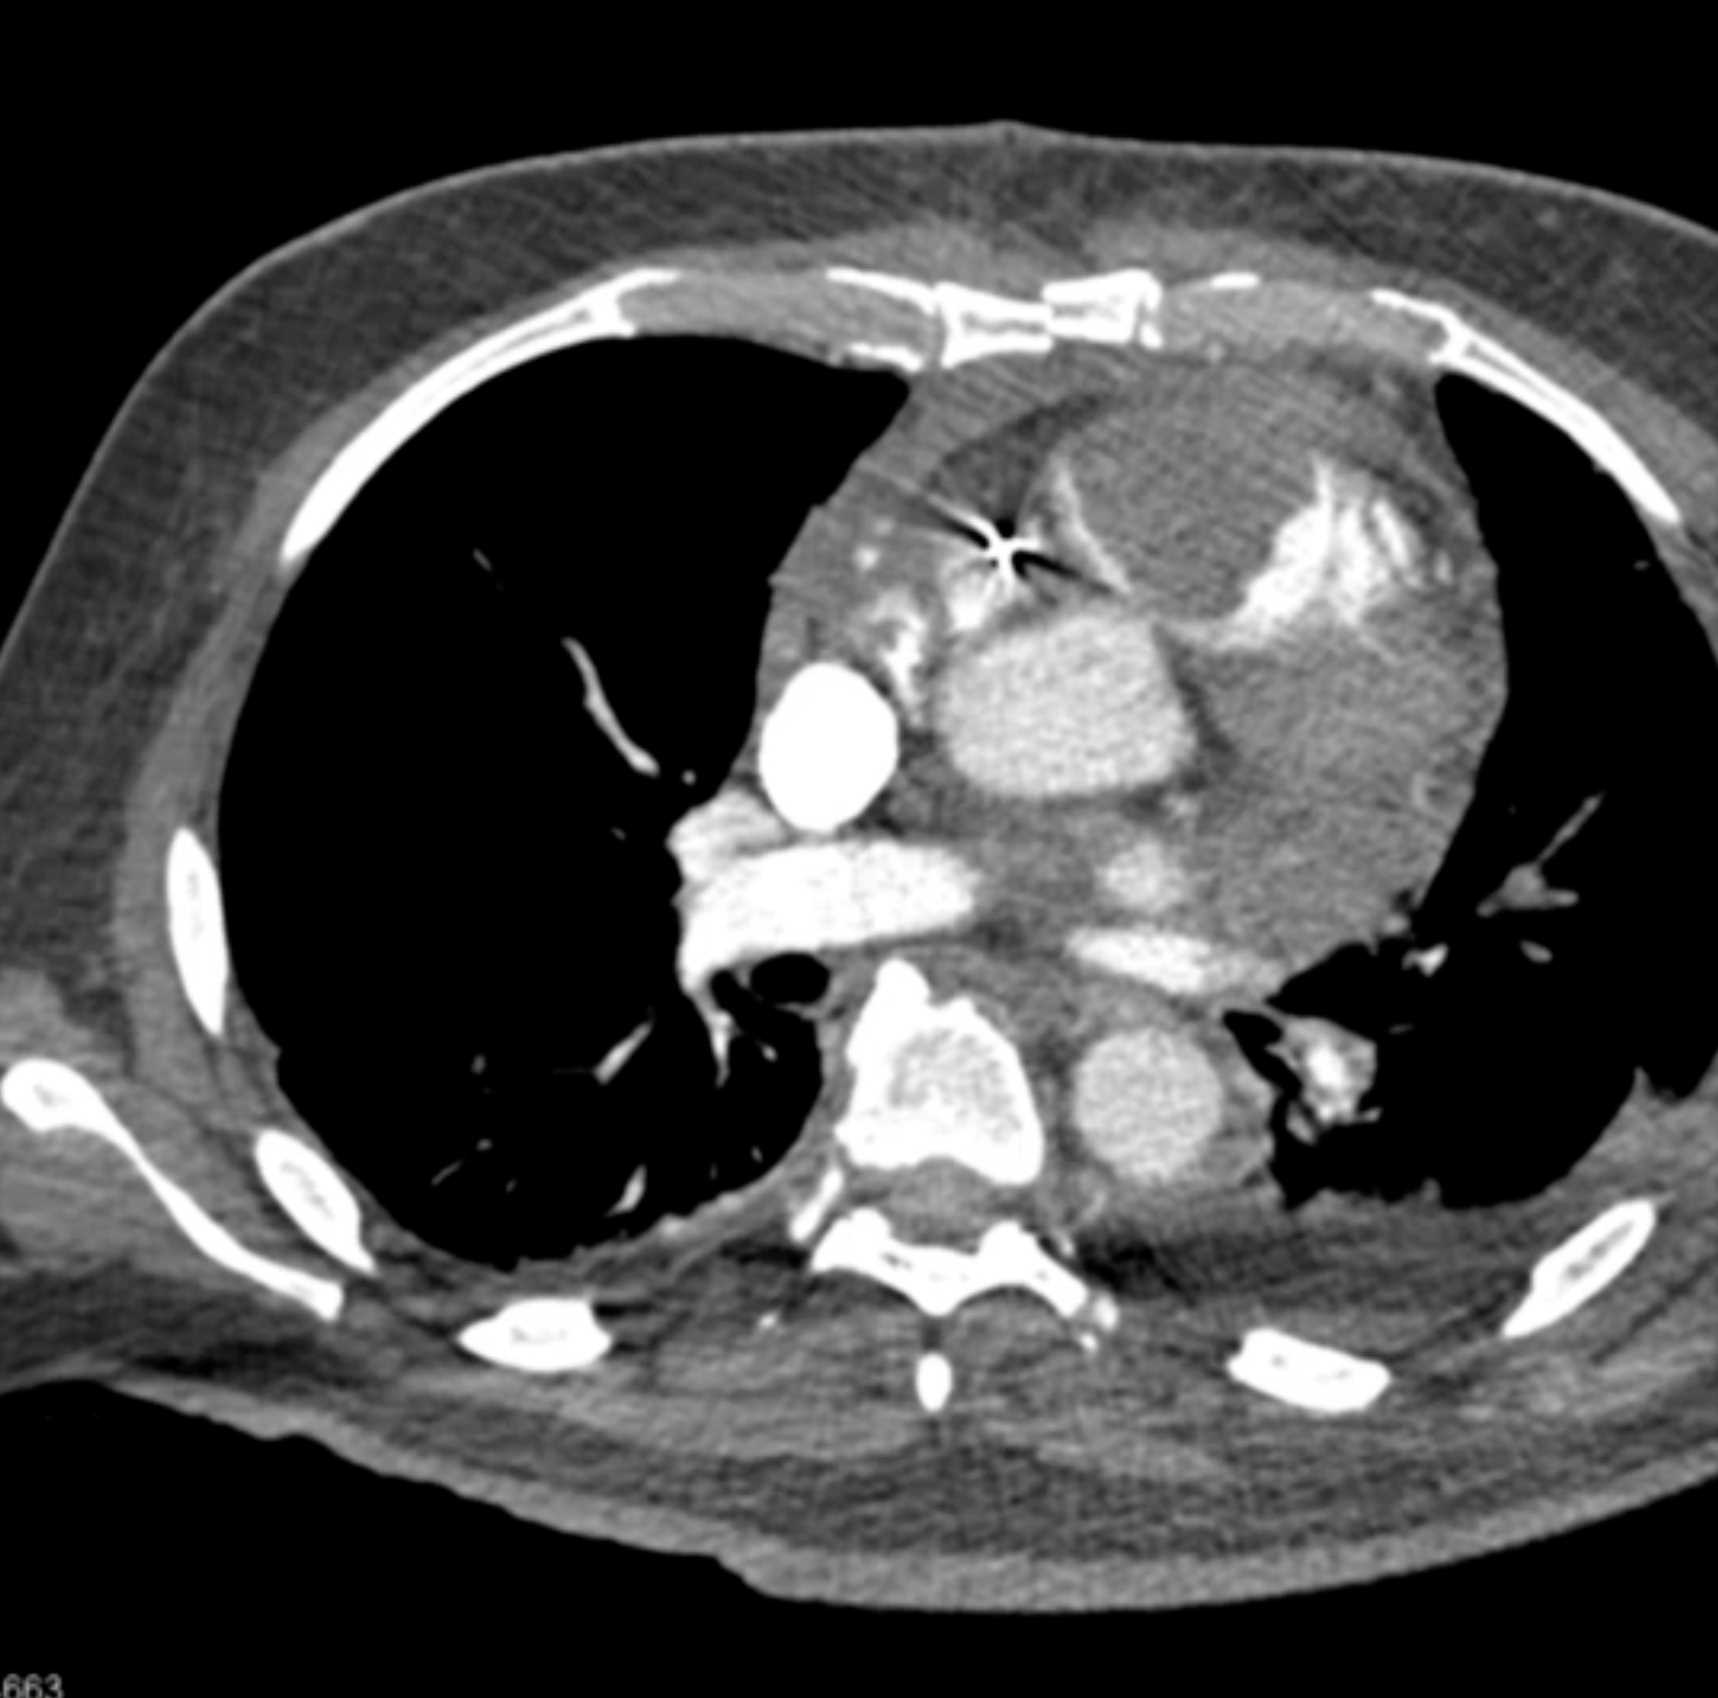

Primary Spindle Cell Carcinoma of the Right Ventricle